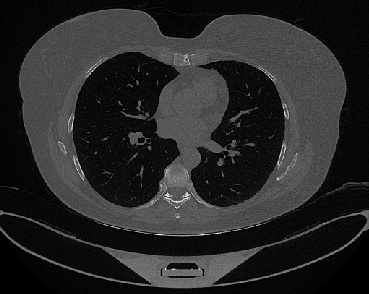

Figure 1 shows four CT scan slices, two from a non-COVID-19 CT scan, on the left and two from a COVID-19 scan, on the right. Bilateral ground glass regions are seen especially in lower lung lobes in the COVID-19 slices.